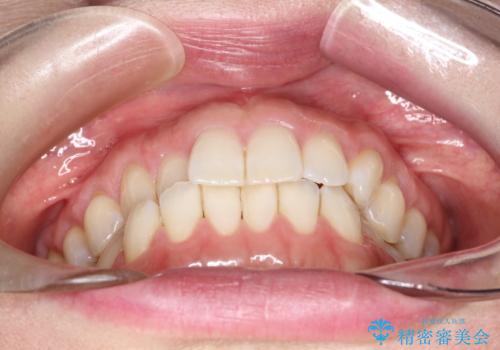

- 右上の前から2番目と3番目の歯が内側に引っ込んでしまっているのを主訴に来院されました。

右上の2番目と3番目のはが前後反対にかんでしまっている状態でした。

内側に引っ込んでいる歯も、インビザラインにてしっかり外側に動かすことができます。